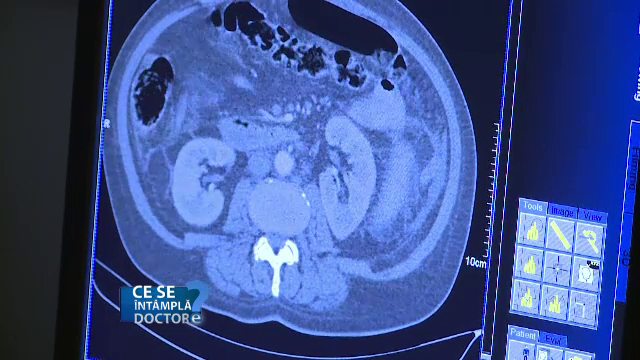

Nu sunt vizibile pe o radiografie banala, dar se pot diagnostica la bronhoscopie sau la examenul computer tomograf. Medicul specialist va indica aceste investigatii, daca veniti la consultatie.